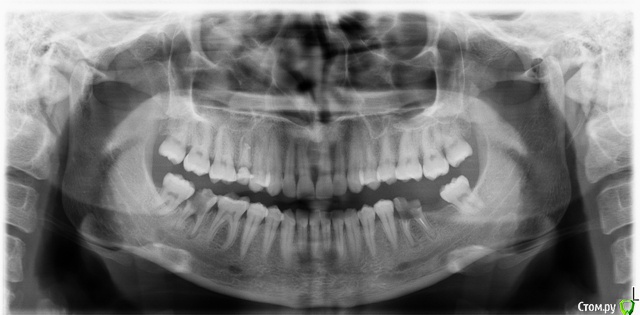

Kattrin Опубликовано 2 декабря, 2017 Поделиться Опубликовано 2 декабря, 2017 Подскажите есть ли шанс спасти зубы или придётся удалять? Рентген прилагаю, думаю сразу попятно о каких зубах идёт речь Ссылка на комментарий

___49___ Опубликовано 2 декабря, 2017 Поделиться Опубликовано 2 декабря, 2017 (изменено) 47, 36 - удалять. 15 - ? плохо видно . решайте вопрос с протезированием - сверху слева предпоследний зуб уже начал выдвигаться вниз из-за отсутствия зуба снизу. Изменено 2 декабря, 2017 пользователем ___49___ Ссылка на комментарий

Kattrin Опубликовано 2 декабря, 2017 Автор Поделиться Опубликовано 2 декабря, 2017 47, 36 - удалять. 15 - ? плохо видно . решайте вопрос с протезированием - сверху слева предпоследний зуб уже начал выдвигаться вниз из-за отсутствия зуба снизу.15-залечен, на нем пломба. 47,36 значит никак не спасти? Ссылка на комментарий

brg Опубликовано 3 декабря, 2017 Поделиться Опубликовано 3 декабря, 2017 15-залечен, на нем пломба.это не значит, что его не нужно лечить. может получится как с 36 и 47 зубами. Ссылка на комментарий

Marika Опубликовано 3 декабря, 2017 Поделиться Опубликовано 3 декабря, 2017 Снимок очень неудачный, но, по-моему, зуб 15 нежизнеспособен. Ссылка на комментарий